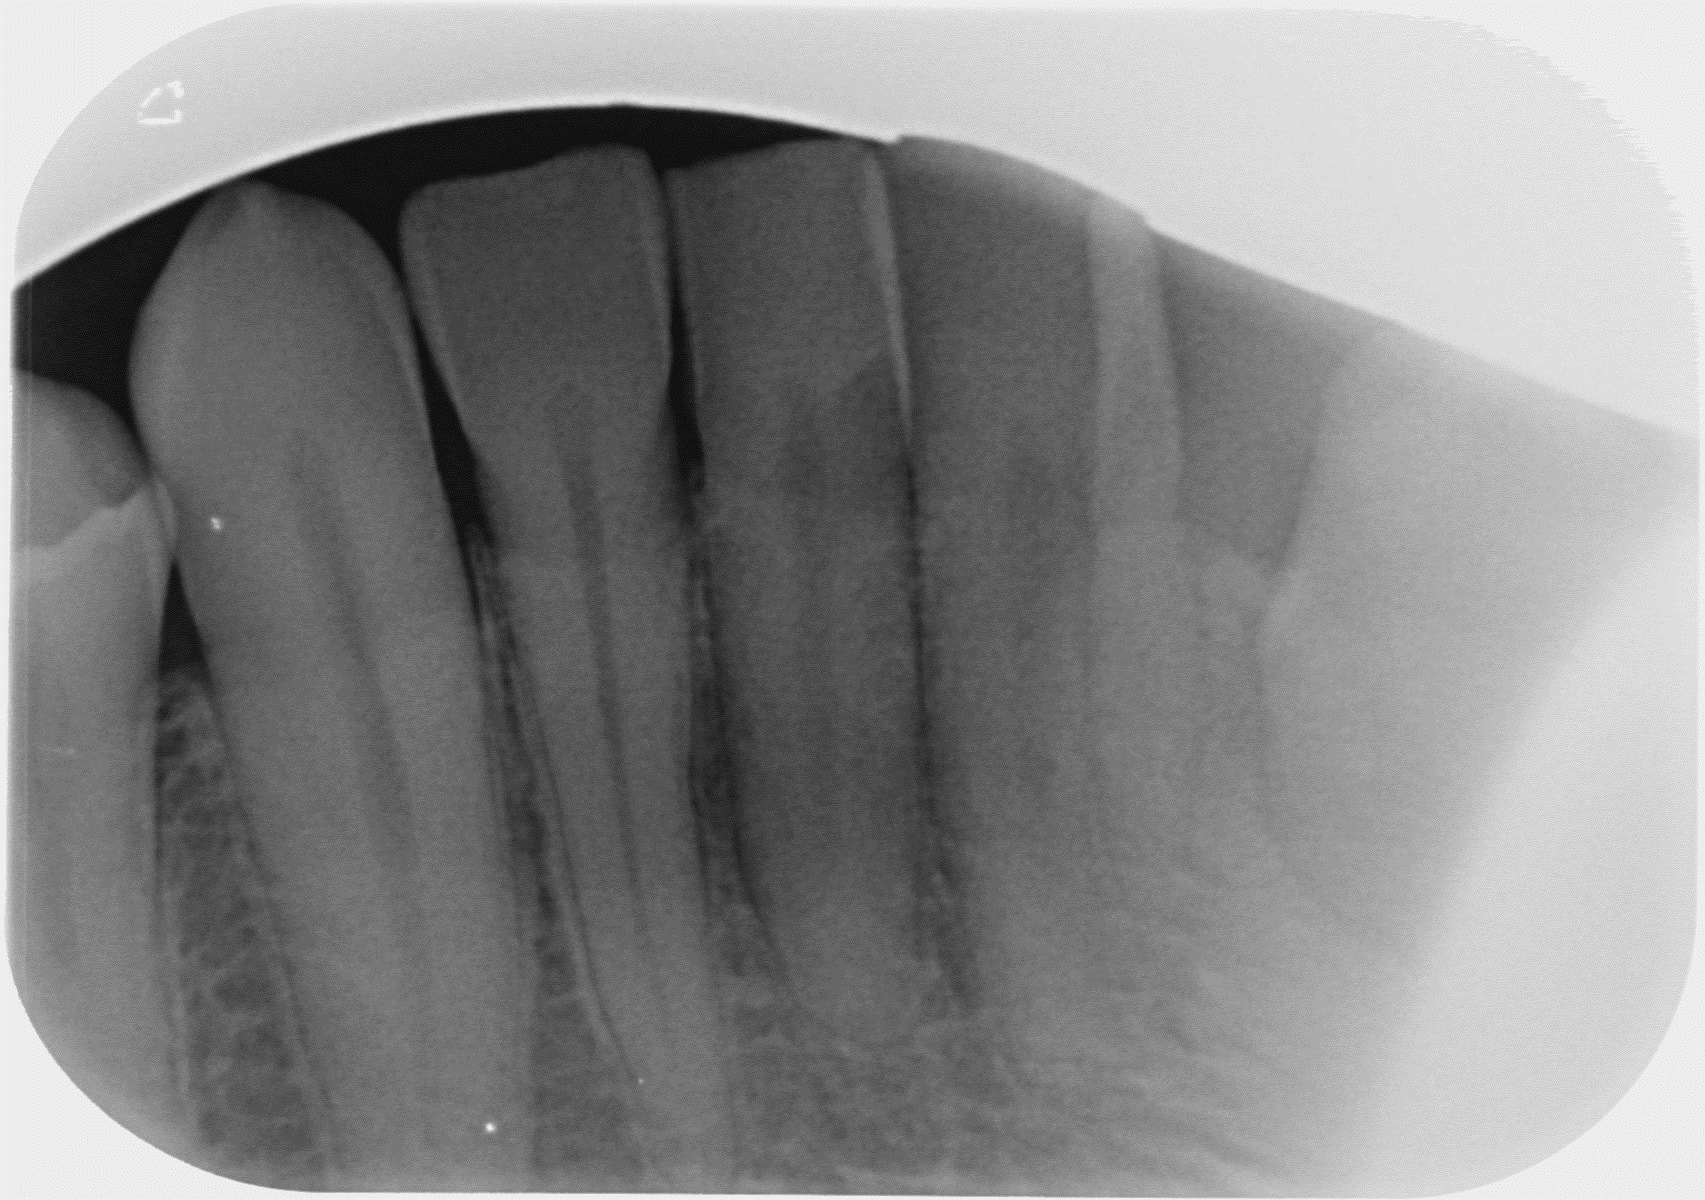

A toutes fins utiles, pour les nouveaux lecteurs, je reposte mes radios.

en ajoutant la 42 également.

Et pourquoi ne pas retraiter la 37 dans un premier temps qui présente une lésion sur la racine mésiale avec un traitement court et une lésion sur la racine distale avec un traitement adéquat?

Bonjour PtnBZ..effectivement l'endo ne va pas jusqu'à l'apex..mais...comme on ne voit pas de tache sombre ..on peut supposer que pas d'infection ?

Sur la radiographie ce n'est pas clair, peut être éliminer les causes les plus probables et les plus simples à régler avant de passer aux moins probables. Ce serait idéal de refaire un examen complet.

1/ une lésion apicale peut ne pas se voir sur une radio 2D c'est si dur à comprendre pour toi ?

2/ 1 seul canal a été traité sur cette 37 alors que c'est rare d'avoir que 2 canaux

3/ on peut avoir des douleurs d'origine endo sans forcément avoir de lésion apicale, hé oui

4/ la 26 n'est pas claire

Le traitement en mésial de 37 n'est pas bon çà se voit tout de suite, peut-être un canal a été oublié, en tout cas un manque d'étanchéité.

Dans un cas comme çà, si cliniquement je vois que la dent est sensible (en écartant la possibilité d'une surocc) et même si le CBCT ne montre rien, je redémonte 37 et refait l'endo, avec le risque effectivement que çà ne change rien mais au moins le traitement sera correct et on peut écarter cette hypothèse à 100%.

C'est marrant que la 37 vous interpelle, alors que la 35 (meme la 45!) est beaucoup plus louche, avec un compo juxta pulpaire (mauvais mariage) , et certainement une mortification lente a bas bruit, le truc bien vicelard au diagnostic differentiel difficile.